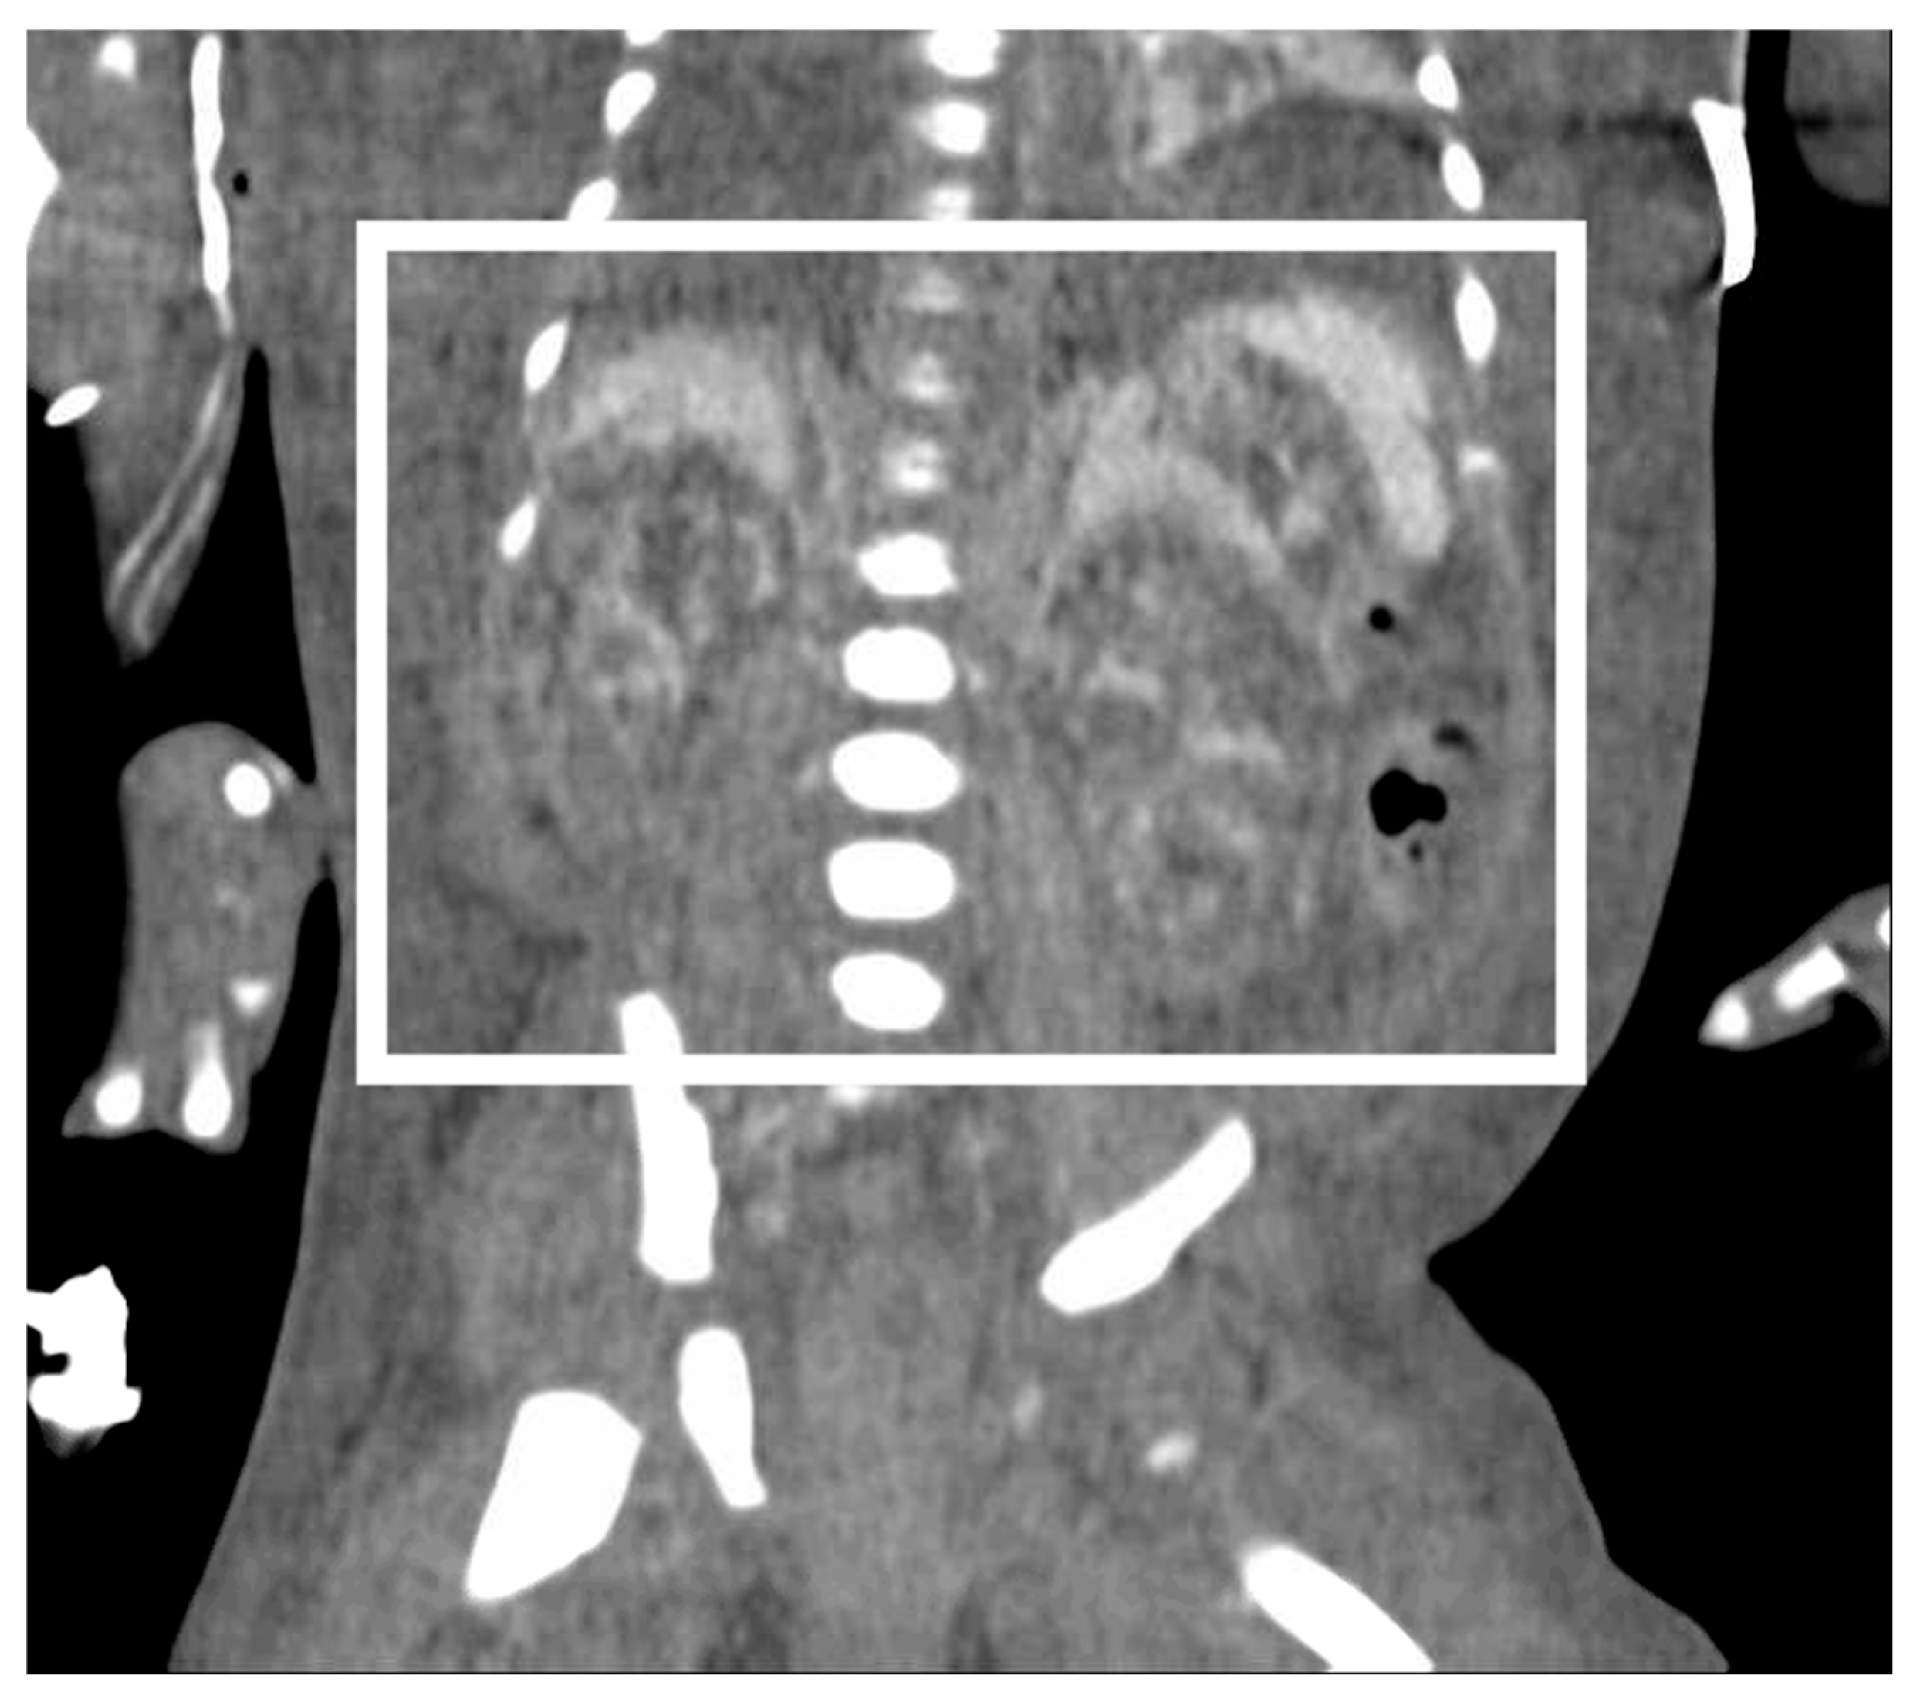

On DOL 5, the patient developed worsening abdominal distention with increased free fluid, rising lactate level, and continued oliguria with minimal brown-colored output, indicating potential bladder rupture. Renal ultrasound at that time demonstrated structurally normal kidneys and ureters, with contusive injuries in the parenchyma (Figure 1 and Figure 2). Pediatric urology was consulted. Diagnostic paracenteses and non-voiding cystogram showed no urinary leak. Computed tomography (CT) of the abdomen and pelvis was performed to further evaluate for free fluid or perforated viscus showed no renal contusion, but noted both kidneys had patchy opacification in the capsule and medulla, consistent with bilateral renal cortical necrosis (Figure 3). Cranial ultrasound was also performed at this time and showed focal parenchymal hemorrhage in the posterior portion of the left frontal lobe (Figure 4).

Figure 3.

Computed tomography image utilizing intravenous contrast on day of life 5 showing bilateral patchy opacification of the external renal capsule and central renal medulla (box).